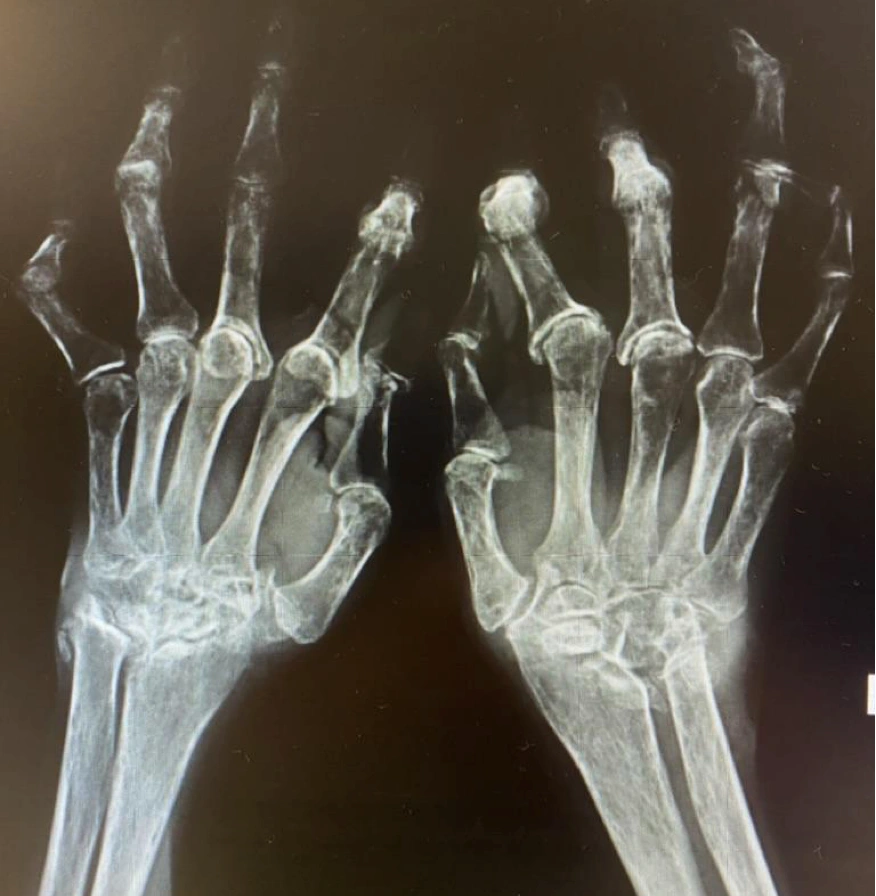

Atención de enfermedades autoinmunes y del tejido conectivo, como artritis reumatoide y lupus. Diseñamos planes de tratamiento integral para aliviar el dolor y mejorar tu movilidad.

La articulación se ve hinchada, caliente y enrojecida. Puede afectar a una o varias articulaciones, y a menudo de forma simétrica (por ejemplo, en ambas manos).

Radiografías que muestran daño articular.